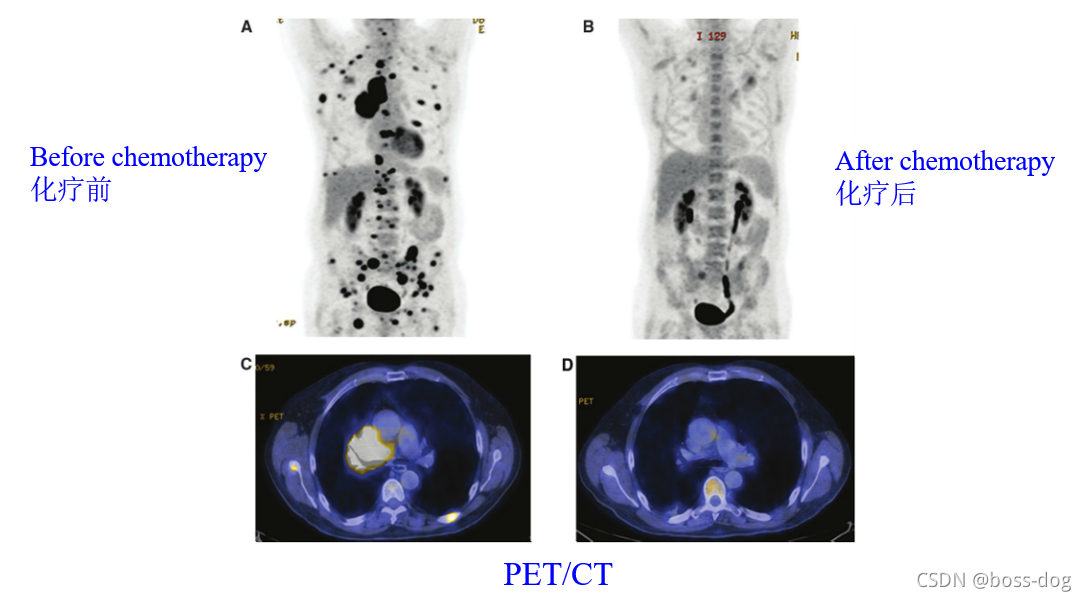

4.核素成像(Radionuclide imaging)。有核辐射,需要采用高能量的X光或者伽马光子;应用领域如单光子平面或成像(Planar single photon imaging)、单光子发射的CT(Single Photon EmissionCT,SPECT)、正电子发射成像(Positron Emission Tonography),这三类都是需要通过往人体里面进行静脉注射一种核素,这种核素需要释放出光子或者释放出正电子来回到它的稳态,如果释放出光子,这光子高能光子穿过人体就会被探测器接收到,然后用来做成像。

Gamma Camera/Scintillation Camera(核素成像)

心脏成像

上图中将两个图像进行一定的融合,左边PET的图像能够把肿瘤的位置给刻画出来,而CT能够把解剖的如人的骨头、肾、肝显示出来,两个图像进行修正和融合就可以看出来肿瘤到底在哪个位置,进行精准定位。